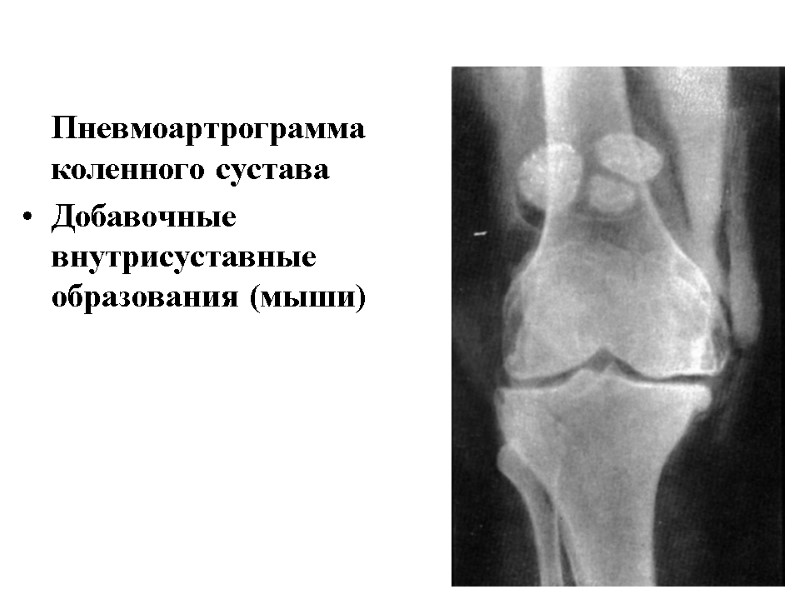

Пневмоартрограмма коленного сустава Добавочные внутрисуставные образования (мыши)